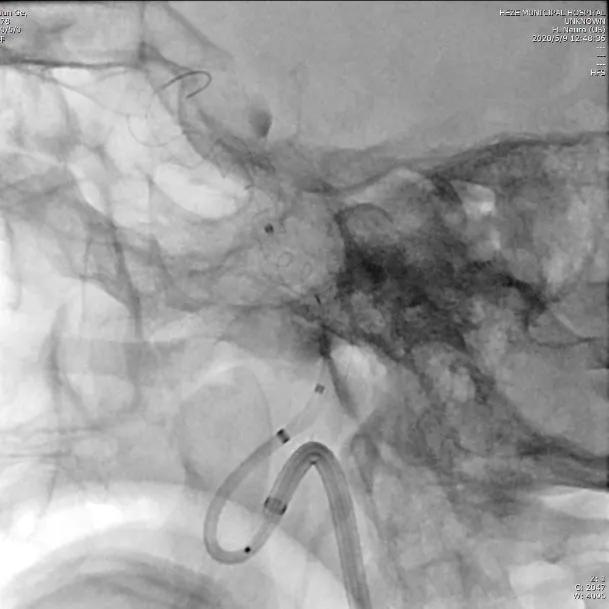

选择5.0×45mm Tubridge®支架,成功释放,覆盖动脉瘤,造影见动脉瘤腔内造影剂明显滞留。

结束手术,患者麻醉清醒后安全返回病房,无神经功能缺失。5天后,患者康复出院。